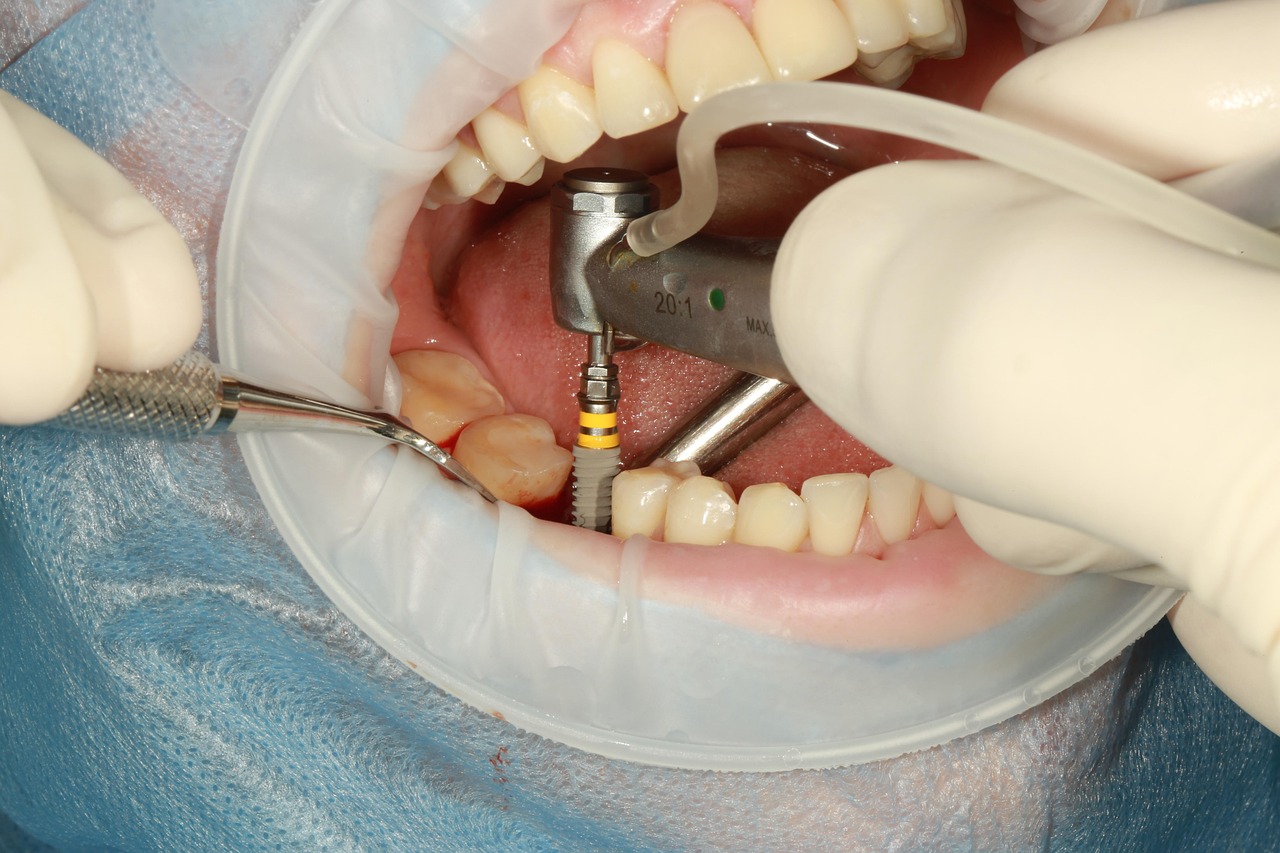

Dental implants are the ideal way to replace a lost tooth. They are long-lasting and are the easiest to maintain.

Similar to Natural Tooth

Looks, feels, and performs most similar to natural tooth